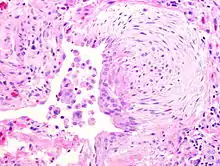

![]() | Squamous cell carcinoma of lung | Micrograph of squamous Cell Carcinoma Lung. A lobule of polygonal squamous cells with moderate amount of eosinophilic cytoplasm and hyperchromatic nuclei are seen. The islands show abnormal keratinization in the form of epithelial pearls in the centre. These epithelial pearls are whorls or eddies of malignant cells with pink keratin in the centre. | Category: Histopathology of squamous cell carcinoma of the lung | Squamous cell carcinoma of lung |